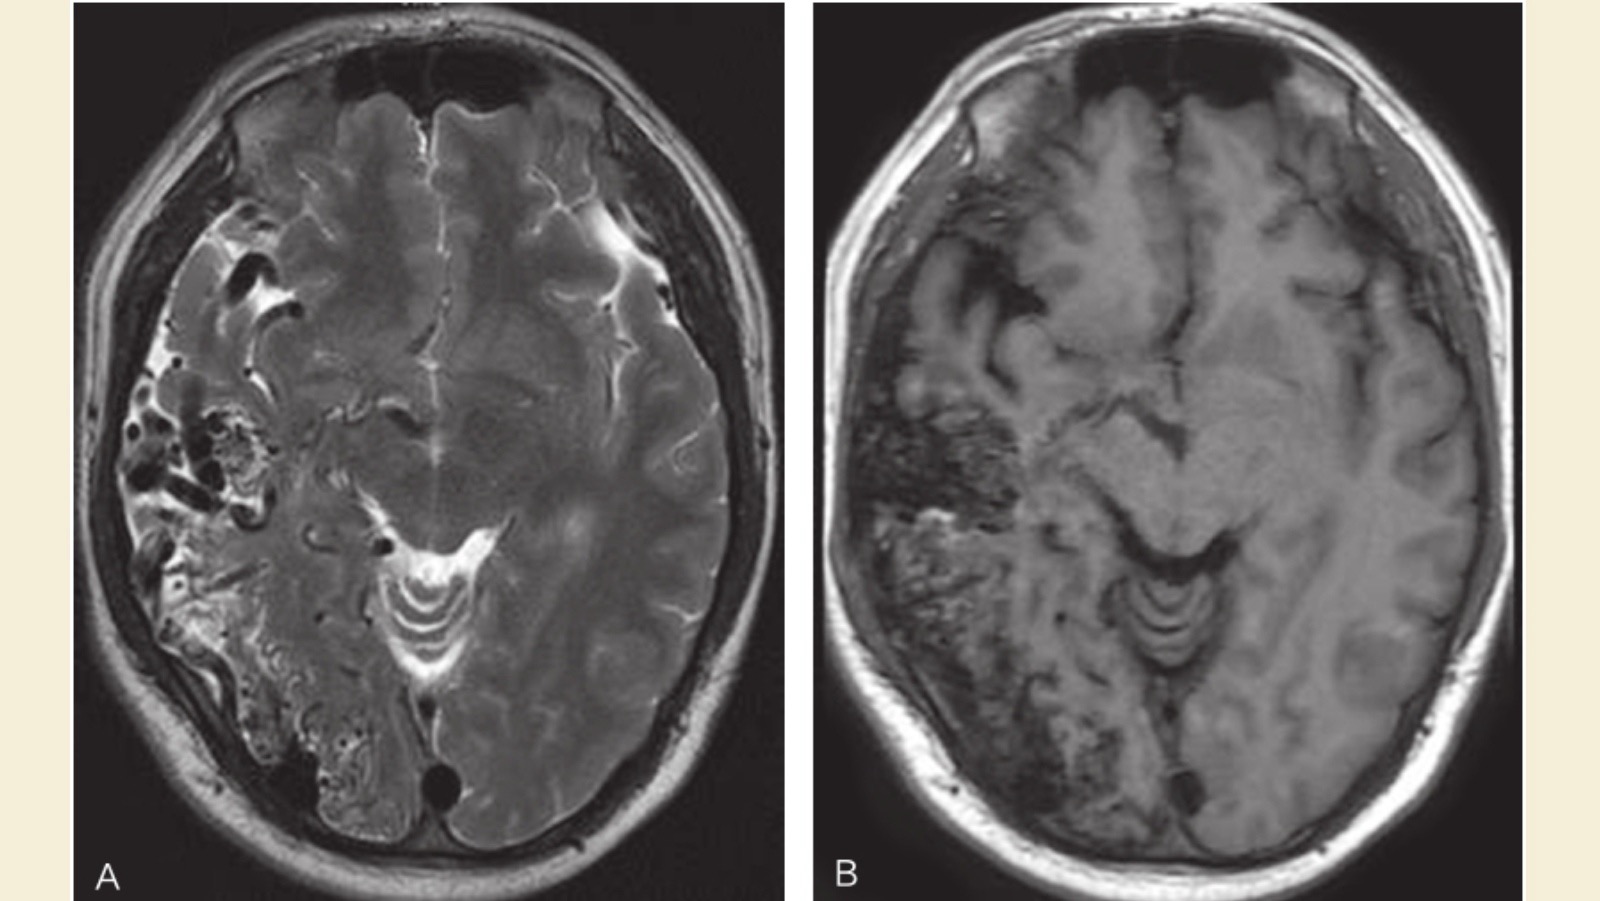

蜂窝样血管流空影,楔形——脑动静脉畸形

圆形流空信号灶脑——动脉瘤

颅内动脉瘤——囊状流空影

动静脉畸形——楔状流空影

- 蜂窝样血管流空影 + 楔形 → 脑动静脉畸形(AVM)

◦ 像一团乱麻:血管纠缠成蜂窝状,血流快,MRI上显示黑色“流空影”。

◦ 位置:多在大脑表面,形状像楔子(尖朝里,底朝外)。

◦ 危险:容易脑出血或癫痫。

- 圆形流空信号灶 → 脑动脉瘤

◦ 像气球鼓包:动脉壁薄弱鼓出一个圆泡,血流在泡里打转,MRI上显示单个黑色“圆点”。

◦ 位置:多在脑底大血管分叉处。

◦ 危险:破裂会突发剧烈头痛(蛛网膜下腔出血)。